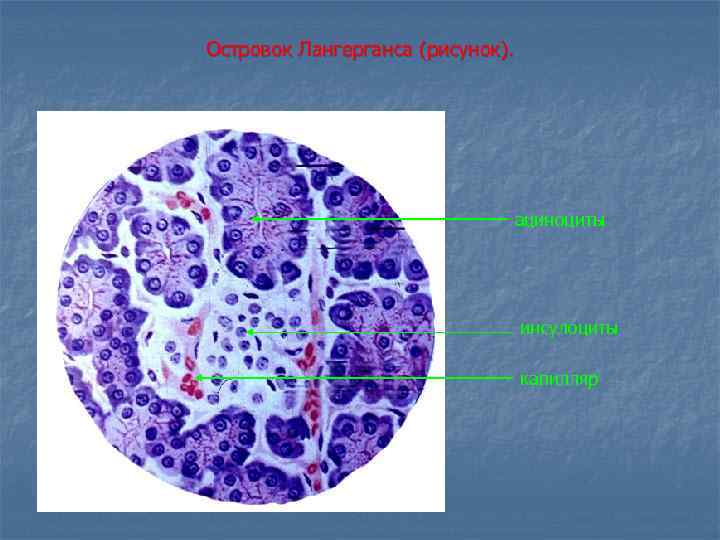

Островок Лангерганса (рисунок). ациноциты инсулоциты капилляр